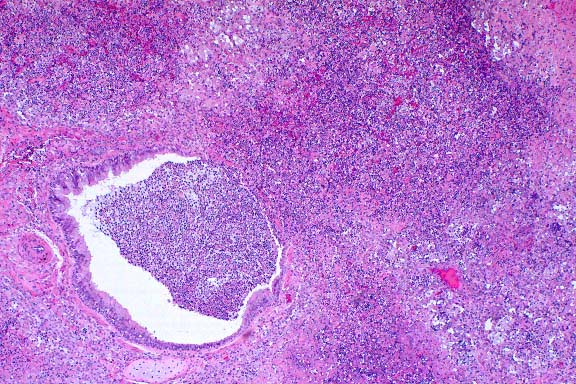

- Case 22-4. Kidney. There is tubular degeneration and

necrosis (vacuolation, karyorrhexis), multifocal neutrophilic

infiltrates in tubular lumens, and mononuclear cells within the

interstitium.

- Case 22-4. Liver. There is periportal infiltration

by lymphocytes, and focal degeneration and necrosis of hepatocytes.